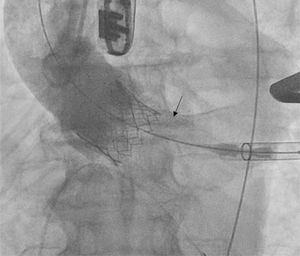

Pre-dilataciónEl efecto mecánico del balón (fractura del calcio y separación de las cúspides fusionadas) incrementa el área del orificio valvular y permite una progresión menos traumática del dispositivo TAVI (fig. 1). Además, acondiciona la válvula para el implante, asegura una expansión uniforme de la prótesis y reduce la fuerza radial. Con ello se consigue reducir la incidencia de malposición y regurgitación perivalvular (RPV). El diseño de las válvulas autoexpandibles les confiere una menor fuerza radial, motivo por el que pueden quedar infraexpandidas al desplegarse sin valvuloplastia previa, máxime en válvulas severamente calcificadas6.

Post-dilatación (fig. 2)Cuando se trata de dirimir cuáles son los resultados clínicos de pacientes sometidos o no a post-dilatación, la evidencia de la que disponemos38-45 nace, una vez más, de estudios no aleatorizados y sesgados. Ello explica la disparidad de sus conclusiones y traduce la necesidad de interpretarlas con cautela.

Existen numerosos escenarios que motivan el planteamiento de la post-dilatación tras el implante de una TAVI. Quizá el más importante (por su elevada frecuencia y repercusión negativa) sea la reducción de la severidad de una RPV, pues el baloneo promueve una expansión óptima de la prótesis (figs. 3 y 4). Con ello, también se consiguen un aumento del área valvular efectiva, una disminución de los gradientes y, en consecuencia, una reducción del mismatch (que se ha asociado a una mayor incidencia de trombosis valvular clínica y subclínica)46.